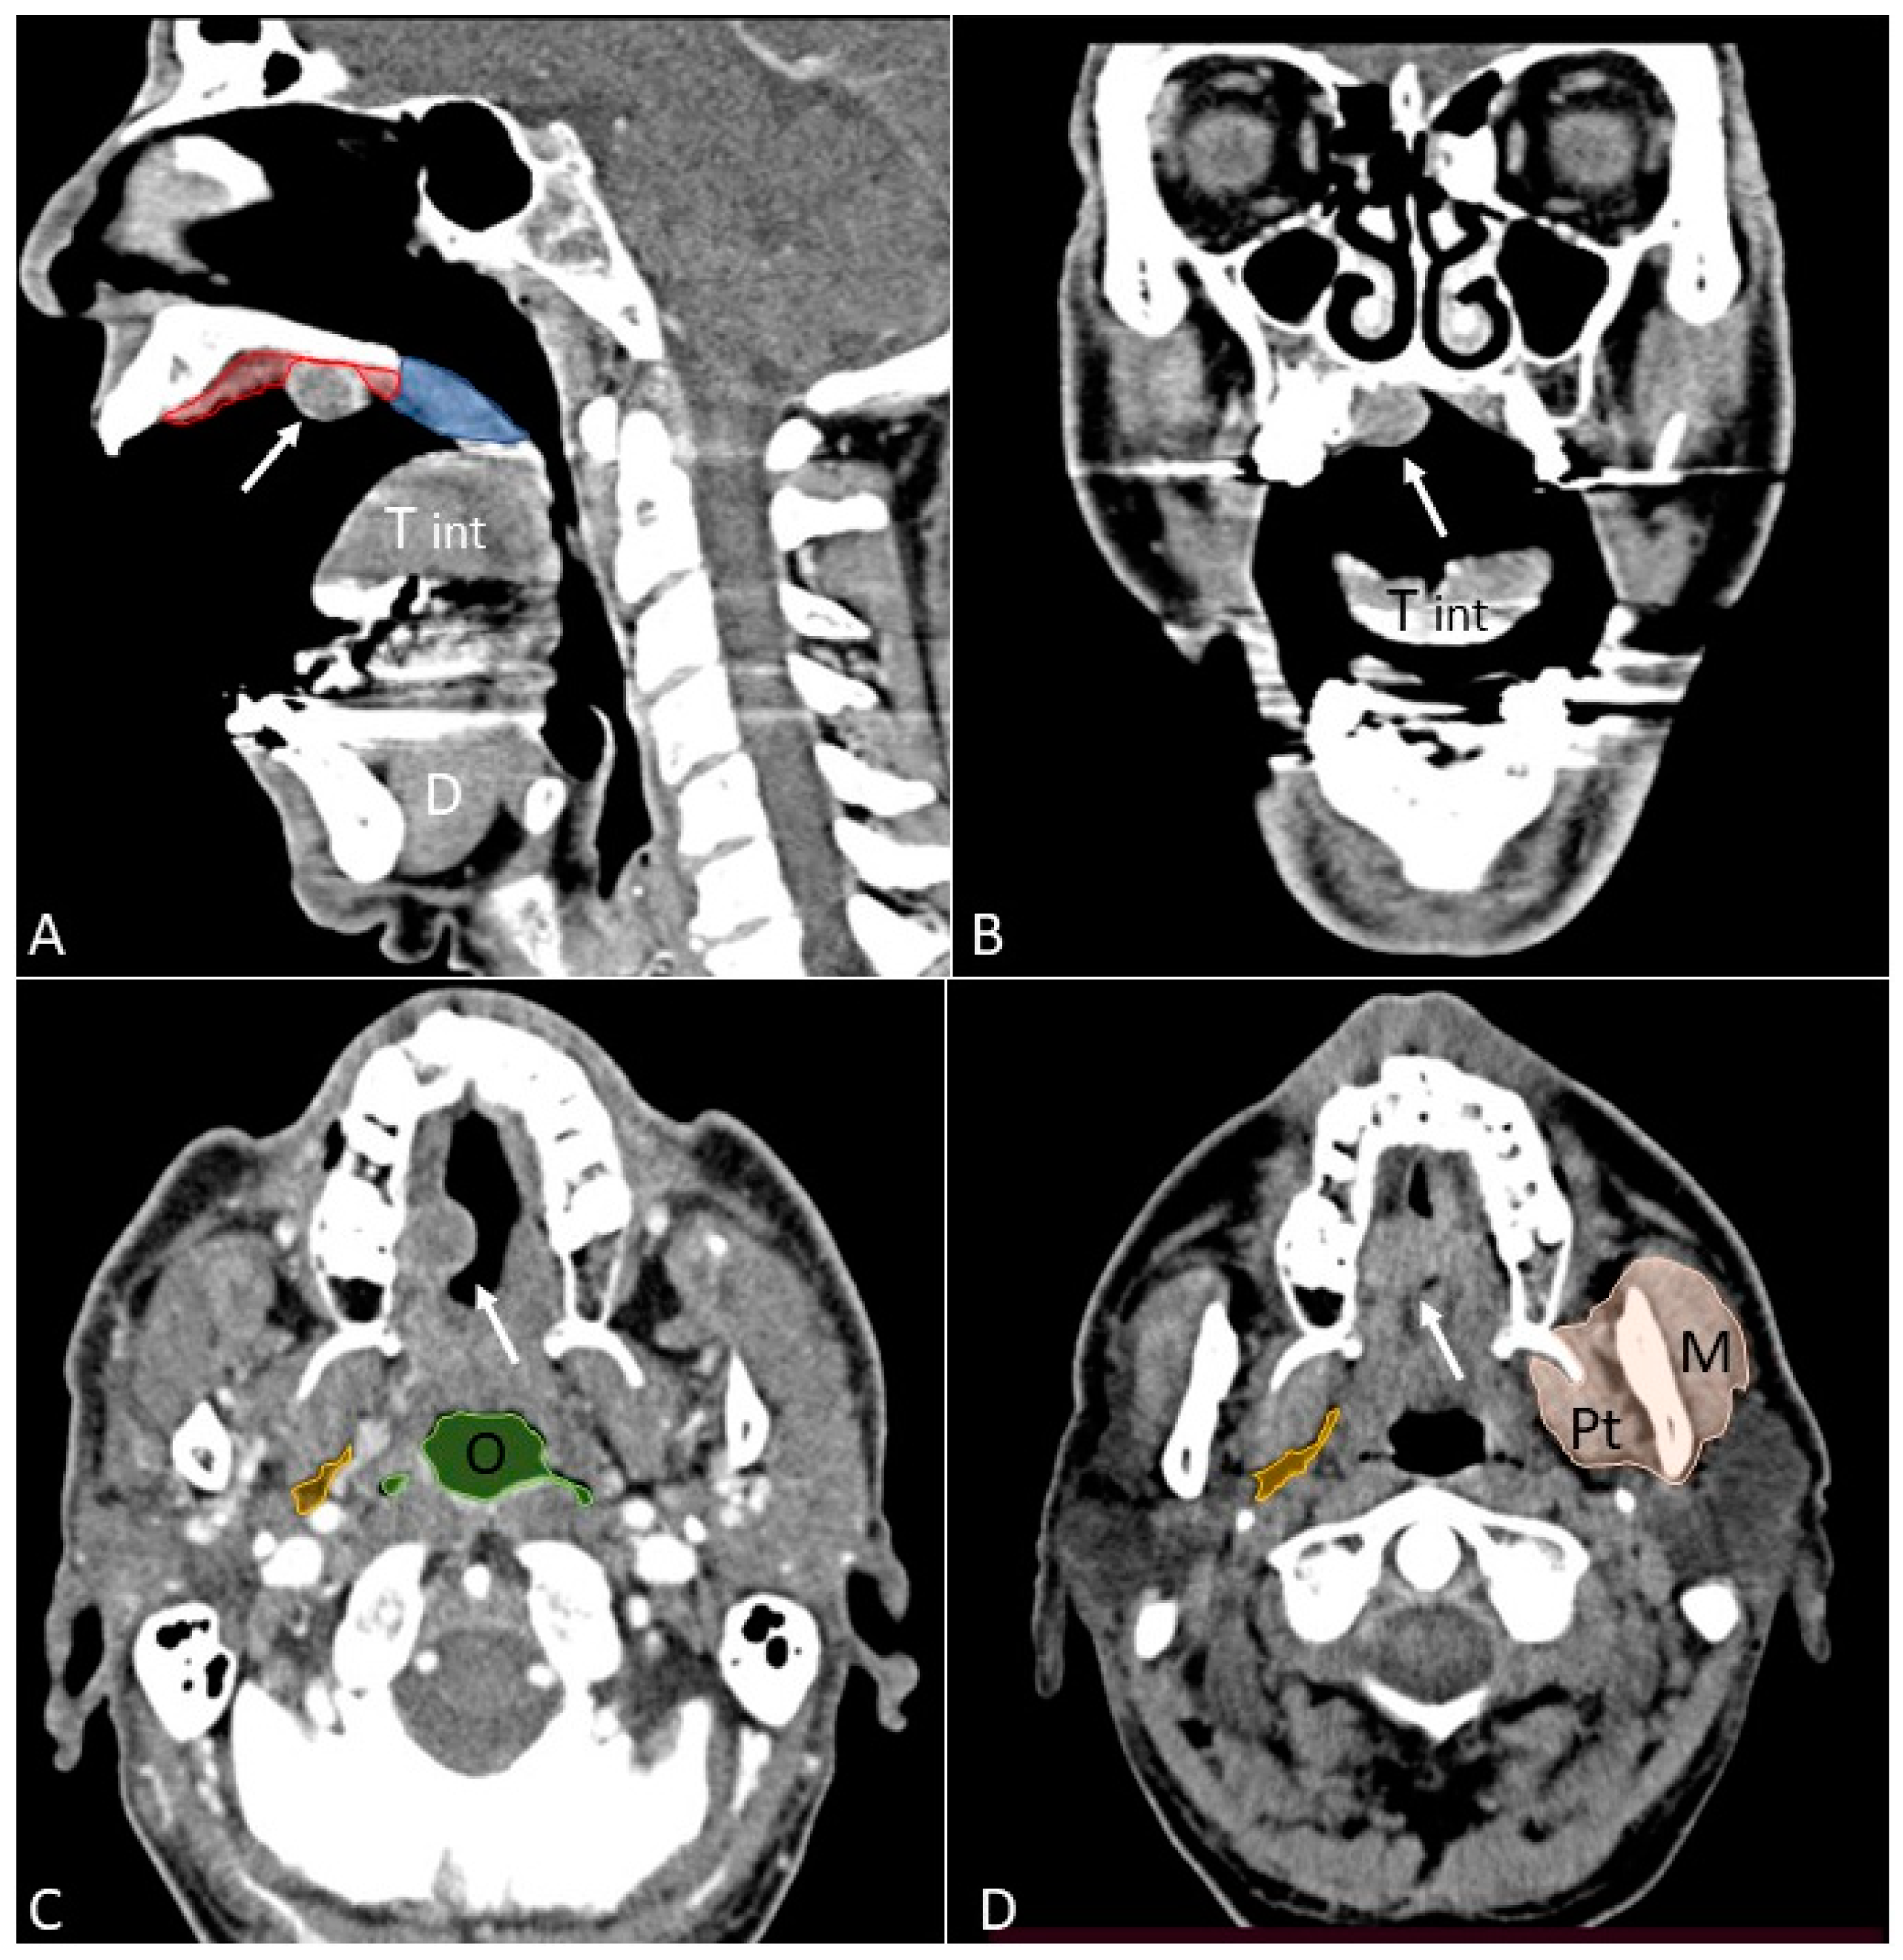

- Open mouth technique. Patients open their mouth and the acquisition is obtained with quiet respiration. A device (i.e., a 50 mL syringe) can be used between teeth to ensure the maintenance of the right position [28]. It allows the separation of the palatal mucosa from the muscular component of the tongue clarifying the exact origin, infiltration, and thickness of tumoural masses (Figure 12 and Figure 13).